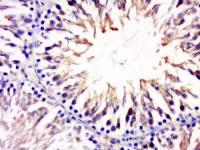

抗体